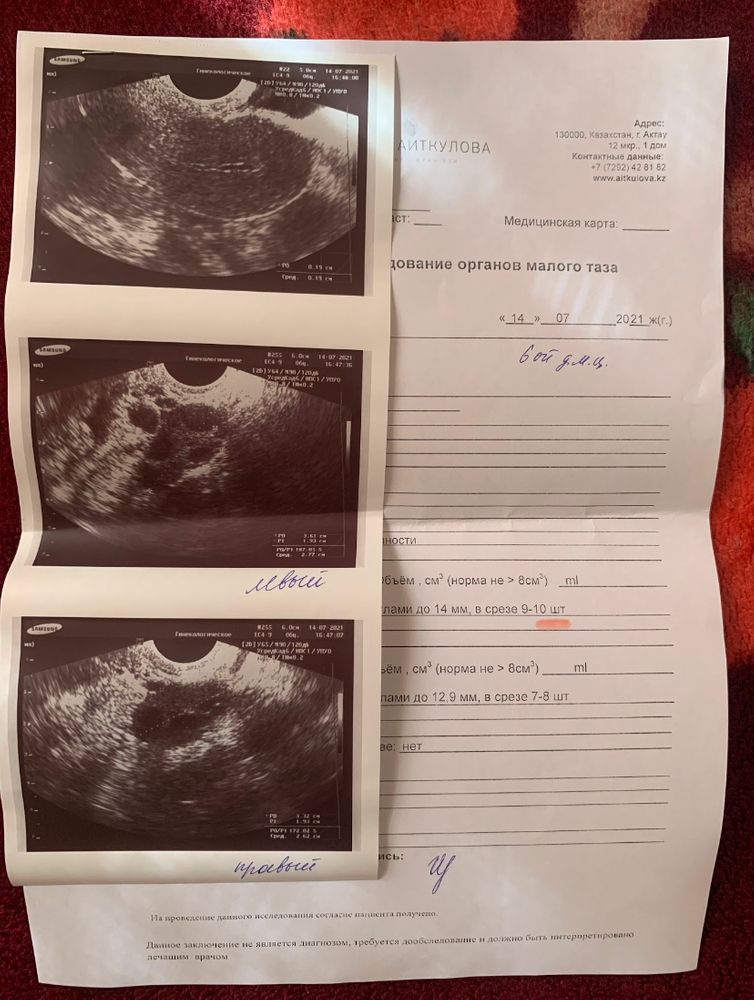

Если уж нормальный узист, он матку, яичники и трубы на одной фотке умещать не станет. Я делала такое же узи, спасибо врачу, сделал фото отдельно и подписал. сходите к другому, пусть все покажет и расскажет Изображение

KUZOVOk, в том и дело что ы заключении стоит под вопросом беременность и всё. Когда входила узист сказала, что не видит ПЯ и возможно внематочная, но я вижу и чёрную точку похожую на ПЯ, и в комментариях некоторые об этом пишут. Почему так сказал узист, не понимаю

Узи трубы не видит вообще ) На фото матка и есть )

Тут на узи только матку вижу на ней я так понимаю плодное яйцо трубы не видно по узи по этому узи очень маленький срок беременности

Я вижу матку и эндометрий

Ангелина, там чёрная точка похоже на очень маленькое плодное яйцо